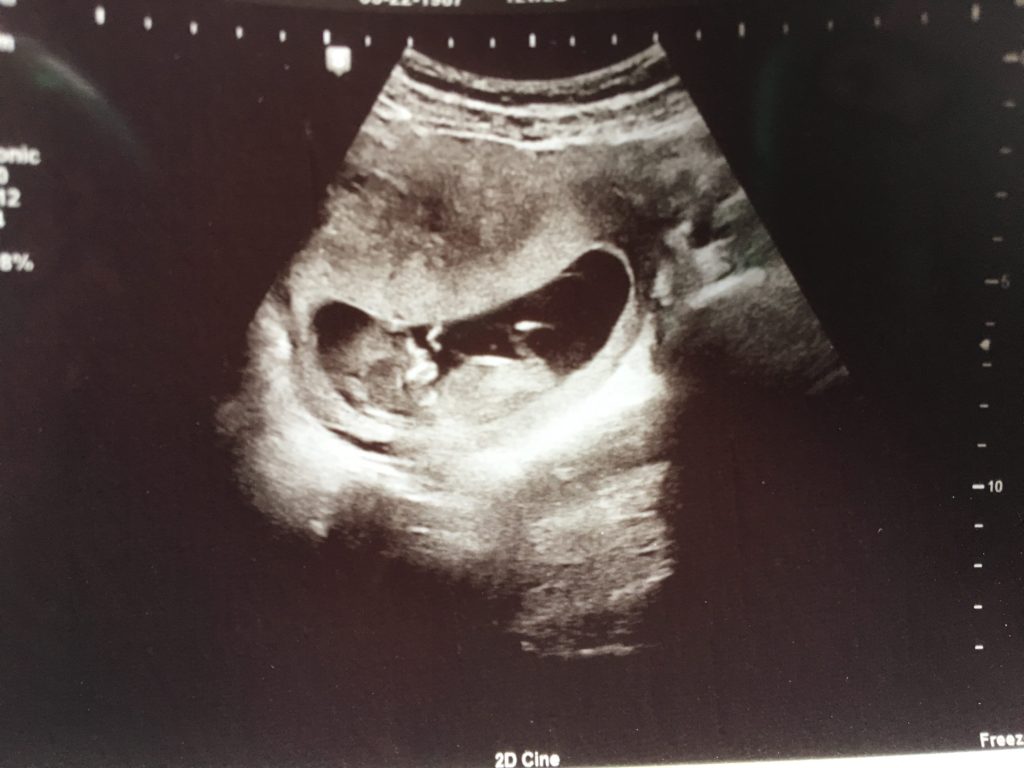

A few months ago, I miscarried. It was early, but I’d known somehow that I was pregnant. When we got the positive result, Casey and I were ecstatic. Thanks to cancer, we weren’t sure we’d even be able to have another baby, so the fact that we got pregnant on the first shot was kind… Read more